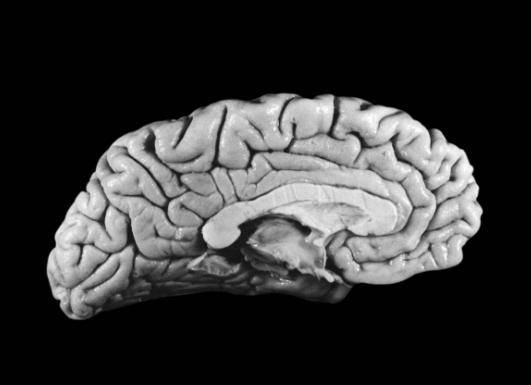

然而,爱因斯坦的天才到底从何而来?在他现存的大脑里究竟隐藏了什么?

较早发表“轻脑”研究成果的是阿拉巴马大学的神经学教授保罗·安德森。经过10余年的研究他发现,爱因斯坦的大脑重量只有1230克(普通男子的大脑一般重1400克),因此他的大脑皮层比一般人薄。

安德森据此推测,爱因斯坦的大脑神经细胞密度比普通人高,使得传递信息的效率大大提高。安德森进而发现,爱因斯坦的右前额叶皮质(运动区)比对照组薄,可是皮质中的神经元数量与对照组无异。换言之,爱因斯坦的大脑皮质中,神经元密度较高。

这个“轻脑”发现有什么意义?安德森教授推论,一是人体的大脑神经元密度越高,则大脑记忆传导速度越快,对于逻辑思维能力的建立越有帮助;二是人体的大脑神经元分布网络越广,则大脑记忆存储量及大脑容积越大,而且人的综合记忆能力越强!也就是说,爱因斯坦的大脑皮质神经元有优异的传导效率与超卓的智慧天才。安德森教授也因这一发现获得了1998年诺贝尔医学奖的提名。

最近,从医学专业杂志《刺针》上传来一则好消息:麻省理工学院著名认知科学家斯帕克初步认定:爱因斯坦的大脑结构与其特殊功能之间存在某种内在联系。斯帕克发现,就在位于齐耳高度、从脑前延伸至后部2/3的下顶叶处,即人脑处理数学思维、三维形象和空间关系等的关键部位,“爱脑”确实与“凡脑”不同:后者的顶叶和颞叶之间通常由“西尔维裂沟”所分裂,形成一道脑上天堑;而“爱脑”的裂纹却在接近顶叶处戛然而止,并急转直上,绕过顶叶不再分裂。于是“天堑变通途”,保持了顶叶的相对完整,而且顶盖骨也模糊不见,因此整个大脑顶叶沟壑纵横,路径曲折,密密麻麻覆盖全脑,联结面积比普通人大约15%。这意味着,更多的脑细胞或神经元更易于联系,可以更好地协调工作。

随后,斯帕克又在《纽约时报》上发表专文,阐明大脑顶叶即每一大脑半球顶端的后部象限,位于初始视觉和体感之间的地方,是空间感的区域。而这也正是爱因斯坦借助“顶叶智力”确定各类事物的部位,从而在下侧小叶或骨叶低处隆起专司抽象数学和空间推理的超凡直觉与优异数值演算能力的区域。

科学家研究发现,爱因斯坦的大脑不仅思维能力超乎寻常,就连脑细胞的形状构造与数量等,都多于或优于常人。据英国《独立报》报道,英国研究人员最近选取4名和爱因斯坦逝世时年龄相仿的男子作为参照对象,把爱因斯坦的大脑切片和他们的大脑进行对比研究,结果发现,除了脑细胞数量多于常人外,爱因斯坦大脑策划的某些部分相对较大,其星形胶质细胞突起也比较大,而且这些胶质细胞末端的神经策划数量也较多。

对爱因斯坦大脑的进一步研究表明,天才来自勤奋。过去,人们一般认为神经胶质细胞的作用就是把神经元集结起来,此外没有其他特别的用途。但近年来研究人员发现,这种细胞在大脑活动中发挥了重要作用,它不仅能够向周围的神经元输送钙,还可以促进神经元间的信息交流。而且,爱因斯坦大脑中每个神经元的胶质细胞数量较多,表明他的大脑对能量的需求和消耗较大,这可能意味着他的思维能力更强。由此可见,爱因斯坦的超凡智慧并非全来自天才,而是来自勤于思考。因为勤于用脑的人,脑血管经常处于舒展的状态,脑神经细胞会得到很好的保养,从而使大脑更加发达,避免了大脑的早衰。

不久前,美国加利福尼亚大学的脑科学博士达利亚·扎德尔在一项“天才与平常人大脑有什么不同”的研究中,特意对爱因斯坦的两块海马区脑切片进行了分析,这个区域主要承担记忆和语言功能。在研究中,扎德尔将爱因斯坦的脑切片与10位普通人的大脑策划进行了比较,这lO位普通人去世时的年龄为22岁一84岁。结果发现,爱因斯坦脑部海马区的左侧神经细胞策划比右侧神经细胞策划大得多,而普通人两侧的神经细胞策划差别不大。

扎德尔的研究认为,海马区左右两侧的大脑皮层正是人类逻辑、分析以及创新思维发生的地方。而爱因斯坦的大脑海马灰质区与普通人有很大区别,说明其左脑海马区和大脑皮层之间神经细胞的联系较之右脑更加紧密,这意味着爱因斯坦的大脑的确与普通人有很大区别。但是扎德尔表示,爱因斯坦脑部左右神经细胞策划不对称的现象到底是他一出生就是这样,还是在成长过程中逐渐演变成这样至今尚不可知。扎德尔还表示:“我也不清楚这种不对称现象到底与爱因斯坦拥有的超常智商之间有什么联系。”

但是在不久前,佛罗里达州立大学人类学系的教授迪安,法尔克在《进化神经科学前沿》上,发表了有关爱因斯坦“枕叶天才”秘密的最新研究发现。迪安说:在针对爱因斯坦大脑10余个策划切片的生化性状与空间模拟的研究中,由于多项实验都指向爱因斯坦的后脑枕叶区域大于常人约20%,于是“枕叶天才”秘密成了最新研究的重点。

迪安指出,在顶部最突起的会合地方就是后脑枕叶区。而他所发现的爱因斯坦后脑中比常人更宽的后脑枕叶区,是视觉、听觉、体觉(来自身体各部分的感觉)和前庭器官神经通路的交会处,被许多科学家认为是人体综合各种感觉,产生更高等的神经、认知活动的地方。由于爱因斯坦的这片脑区较大,因此他有着超于常人的优异视觉空间认知、数学能力和运动想象能力。

为此,加拿大麦克马斯特大学的教授桑德拉·维特森最近研究发现,爱因斯坦大脑颞叶里一块主管语言的区域,其较宽区域的神经元密度低于常人,这就能够解释爱因斯坦白幼不善于用语言交流的原因。维特森进而推论,爱因斯坦后脑颞叶下部的区域比一般人宽,也影响了邻近主管语言区域的发展。其实,作为史上最伟大的理论物理学家之一,爱因斯坦的抽象能力是超凡的。而他曾经说过,自己几乎不以语言文字的方式思考,而是像放电影一样用图画般的想象力来思考问题,这与他较宽的后脑颞叶下部区的想象与空间认知功能恰好呼应。

揭开爱因斯坦大脑“侧顶叶”超理性思维奥秘的,是加利福尼亚大学伯克利分校的神经学教授玛丽安·戴蒙德博士。她认为,对小鼠的多项实验证明,大脑是位讲究效率的秘书。由此她将爱因斯坦的大脑切片和11位普通人的大脑切片对比后发现,爱因斯坦大脑位于左侧顶叶的那块标本里,其中神经细胞策划对神经元的比例,比普通人的要多73%以上。这一实验结果发表在1985年出版的《实验神经病学》杂志上。

获得这一实验结果后,戴蒙德博士开始了一系列关于爱因斯坦“侧顶叶”超理性思维奥秘的探索,至今的各种调查与研究的结论是:智力的高低并不取决于脑的大小,而取决于脑中各个神经细胞策划的数量多少以及轴突与神经元发生的复杂程度。这一结论说明,才华横溢的爱因斯坦在展示他非同寻常的超理性思维能力时,有一种非常活跃又能力非凡的智慧能力。

关于爱因斯坦大脑“下叶区智慧”的研究也有新的发现。不久前,由加拿大麦克马斯特大学教授桑德拉,威尔特森领导的研究小组发现,位于爱因斯坦后脑左右半球的上部顶下叶区域比常人大15%,其机理非常发达。这项研究成果发表在著名医学杂志《柳叶刀》上,认为爱因斯坦的天才是天生的,并非全靠后天用功求学得来,证实后天的努力虽然也能成才,但天生天才也是事实。大脑中负责视觉思考和空间推理的顶下叶区域发达,对一个人的数学思维、想象力以及视觉空间认识都发挥着重要作用。这一研究解释了为何爱因斯坦有独特的抽象思维与过人的空间认知能力——左右半球的上部顶下叶区域比常人要大。

斯帕克指出,爱因斯坦大脑左右上部顶下叶区一般大,二者都大于常人15%,而脑重不增。有了这个完整、宽大的小叶,即可通过千百万突触所构成的微循环,容纳更丰富也更紧凑的空间与数学推理的逻辑思维线路。因此,思维敏捷、思路活跃的爱因斯坦之所以成为绝世天才,很可能是胎儿发育早期自然形成的。

为了探寻天才之所以成为天才的原因,由美国加利福尼亚大学伯克利分校的神经科学教授戴蒙与佛罗里达州立大学人类学系的教授迪安·法尔克联合领导的研究小组,最近通过化石分析技术重建了爱因斯坦的脑部轮廓,首次展示出爱因斯坦大脑皮层中十几个与常人不同的特异细微之处。而这些区别,也许就是爱因斯坦能以全新视角诠释物理学的智慧奥秘所在。

特异之一:作为研究古人类神经中枢演变过程的权威专家,戴蒙教授发现爱因斯坦大脑顶叶区域的皮层高低起伏与众不同,暗示着爱因斯坦脑部那些与数学、视觉、空间认知有关的皮层经过了重新分布。

特异之二:爱因斯坦大脑不仅在左右上部顶下叶区比一般人大15%,更不寻常的是顶下小叶区缺少常人都有的一条特殊的裂缝,导致两块关键的脑部区域成为一个整体。有了这个完整、宽大的小叶,即可通过千百万突触所构成的微循环,容纳更丰富也更紧凑的空间与数学推理的超凡逻辑思维缨路。

特异之三:这是最令人类学教授迪安·法尔克兴奋的发现,在爱因斯坦大脑虚拟展示的运动皮质照片上可以看到类似球形突起状的构造。迪安认为,在专业钢琴师和小提琴手的神经中枢上也发现过类似的结构,那是长时间的手部锻炼引起的。这可能与爱因斯坦从小接受的小提琴训练有关。

特异之四:一般人的大脑里有一条叫做“外侧裂”的脑沟穿过这里,沟的尾稍嵌入一块名为“缘上回”的区域。而在爱因斯坦的大脑照片上则显示,他的“外侧裂”在进入顶叶下部区域之前就与另一条脑沟合并,“缘上回”也显得更为完整。维特森认为,一般情况下,大脑中神经连接密集的地方形成凸起的脑回,而神经连接比较稀少的地方则凹下变成脑沟。爱因斯坦戛然而止的外侧沟,正好说明他的顶叶下部区域比一般人的神经连接更密集。

特异之五:这是迪安·法尔克在《进化神经科学前沿》上发表的最新研究成果。爱因斯坦大脑表层的很多部分没有凹沟,因此神经细胞可以通行无阻地沟通,思维也能够活跃无比。维特森指出,爱因斯坦大脑的顶叶异常发达,在形态上也有特异之处,例如侧脑裂并不明显,特别是左半球。因此顶叶下段皮质中的神经元易于相互联系,使爱因斯坦在视觉、空间认知、数学思考、运动知觉这些认知领域中,表现出超卓的智力。

特异之六:法尔克还发现,爱因斯坦大脑两侧顶叶区域的凹槽和凸起模式十分罕见。她由此推测,这在一定程度上可能同爱因斯坦善于把物理问题概念化的卓越才能有关。她指出,爱因斯坦作为“综合性思想家”的才能可能源于他大脑顶叶不同寻常的结构。这项研究成果刊登在最新一期的《进化神经科学》杂志上。

许多科研人员说,爱因斯坦大脑结构展现的“九大奥秘”也许并非独一无二,其左右半脑与再分区的额叶、顶叶、枕叶、颞叶,以及脑细胞末端神经策划更多的特点在其他人的大脑中也可能存在,只不过其他人从未有“用武之地”而已。但是,科学家提醒说,大脑结构不宜完全被看成是一种智力标志,“某些人的心智在很大程度上取决于社会因素,其个体潜能的全面实现依赖于多种后天和环境因素”。